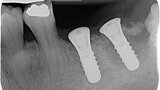

Fig. 8: Postoperative radiograph of implant placement.